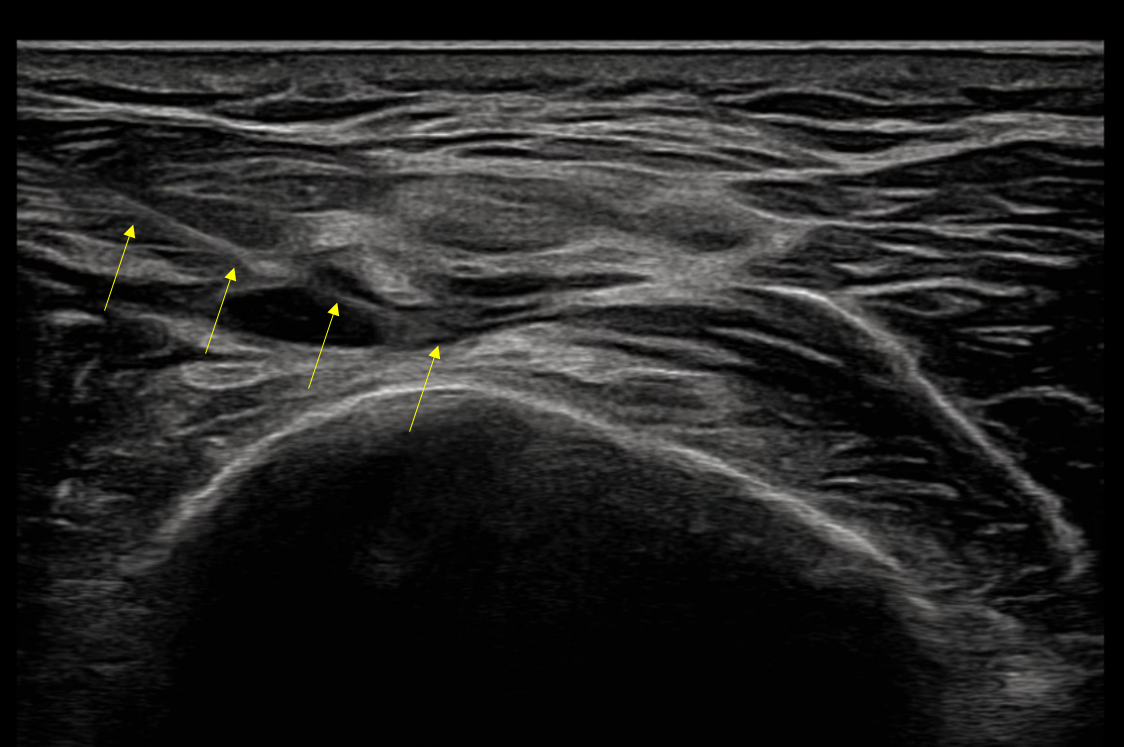

The lecture begins with a structured overview of the major peripheral nerves of the lower extremity and their ultrasound appearance. Emphasis is placed on identifying key anatomical landmarks and recognizing spatial relationships between nerves, surrounding muscles, fascia, and vascular structures. This foundation supports accurate nerve identification and safe procedural planning.

Learners are introduced to systematic scanning methods used to locate and track major peripheral nerves in the lower limb. The session highlights probe positioning, longitudinal and transverse scanning approaches, and practical techniques for optimizing image quality and anatomical orientation.

The lecture compares in-plane and out-of-plane needle approaches used during ultrasound-guided pharmacopuncture. Emphasis is placed on needle trajectory planning, maintaining real-time needle visualization, and selecting the appropriate approach depending on anatomical conditions.